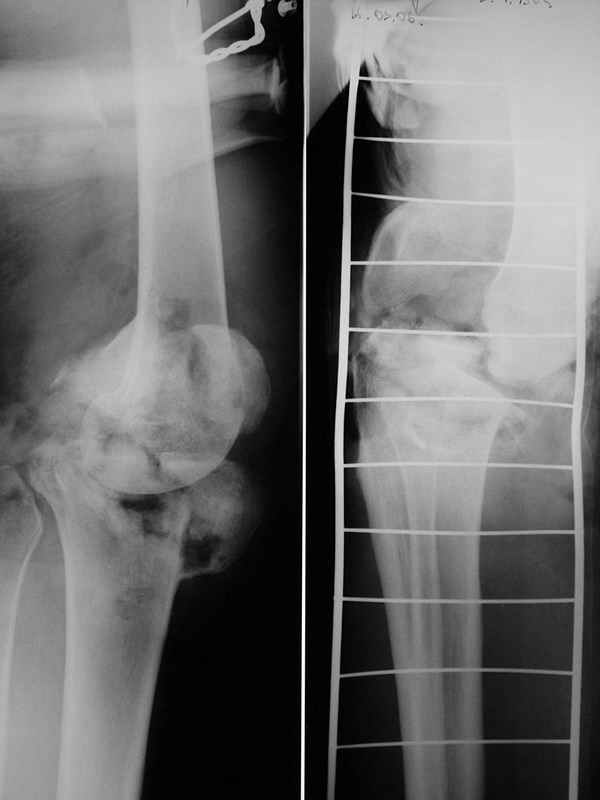

Больной 48 лет, соматически здоров, около 3 недель назад получил тяжелый открытый перелом внутренних мыщелков бедра и большеберцовой кости. Травма производственная - наехал бульдозер.

При поступлении - травматический шок 2 ст. При ревизии раны - отсутствие внутреннего мыщелка бедра, перелом внутреннего мыщелка б/б кости, нестабильность коленного сустава. Повреждений магистральных сосудов и нервов нет. Рваная лоскутная рана по внутренней поверхности колена. Выполнен адаптационный остесинтез остатков кости спицами и мостовидная трансартикулярная фиксация стержневым аппаратом внешней фиксации. Наводящие швы, частично - пластика по Хохутову. Сейчас раны заживают (местами с небольшими некрозиками, но в целом неплохо), встает вопрос о втором этапе лечения. Напрашивается вроде артродез коленного сустава.

Возможно кто-либо имеет опыт лечения подобных случаев и может предложить нечто повеселее?